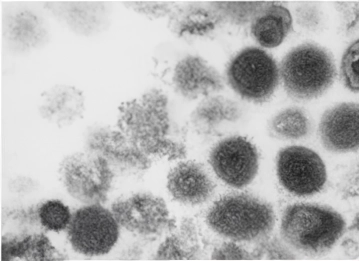

エムポックス(サル痘)の現状とネズミによる今後の危険性